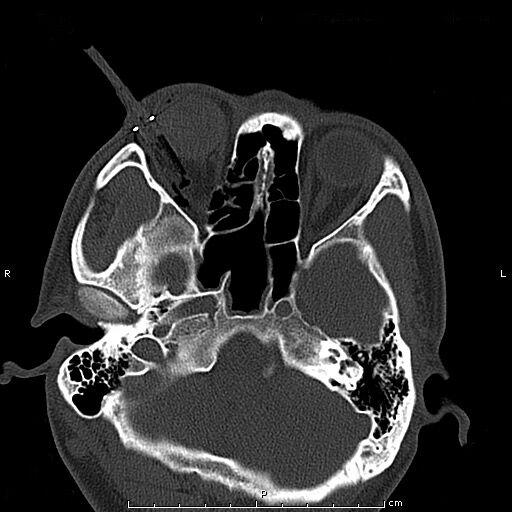

患者青年男性,因“右眼被钢笔戳伤2小时余”入院,眼科查体:视力:右无光感,左0.4。眼压:右不能检查,左正常。右眼上睑红肿,钢笔自颞上方眼睑刺入,末端位置不详,睁眼困难;结膜充血、水肿,角膜尚清,前房积血,余眼内结构窥不入。左眼未见明显异常。入院后完善眼眶CT检查,印象:右眼眶异物并右眼球破裂伤、眶内壁骨折,异物嵌顿于眶壁。钢笔内含墨水,伤情重且复杂。